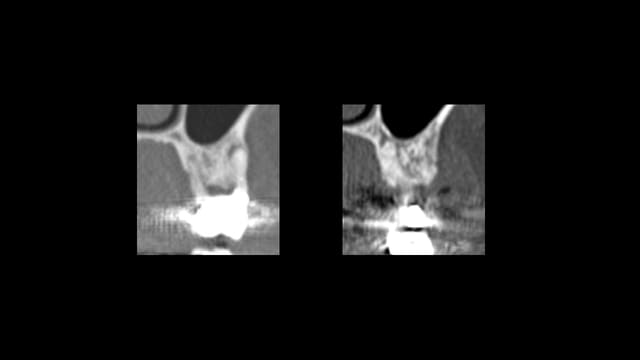

Scanner de contrôle quelques mois plus tard...

Preservation de crete - Eugenol

la procédure a permis de conserver le volume osseux disponible voir même l'augmenter, la difficulté est que le produit de comblement est radio-opaque et que sa cohésion est délicate à aprécier. peut -tu faire part de tes sensations lors du forage.